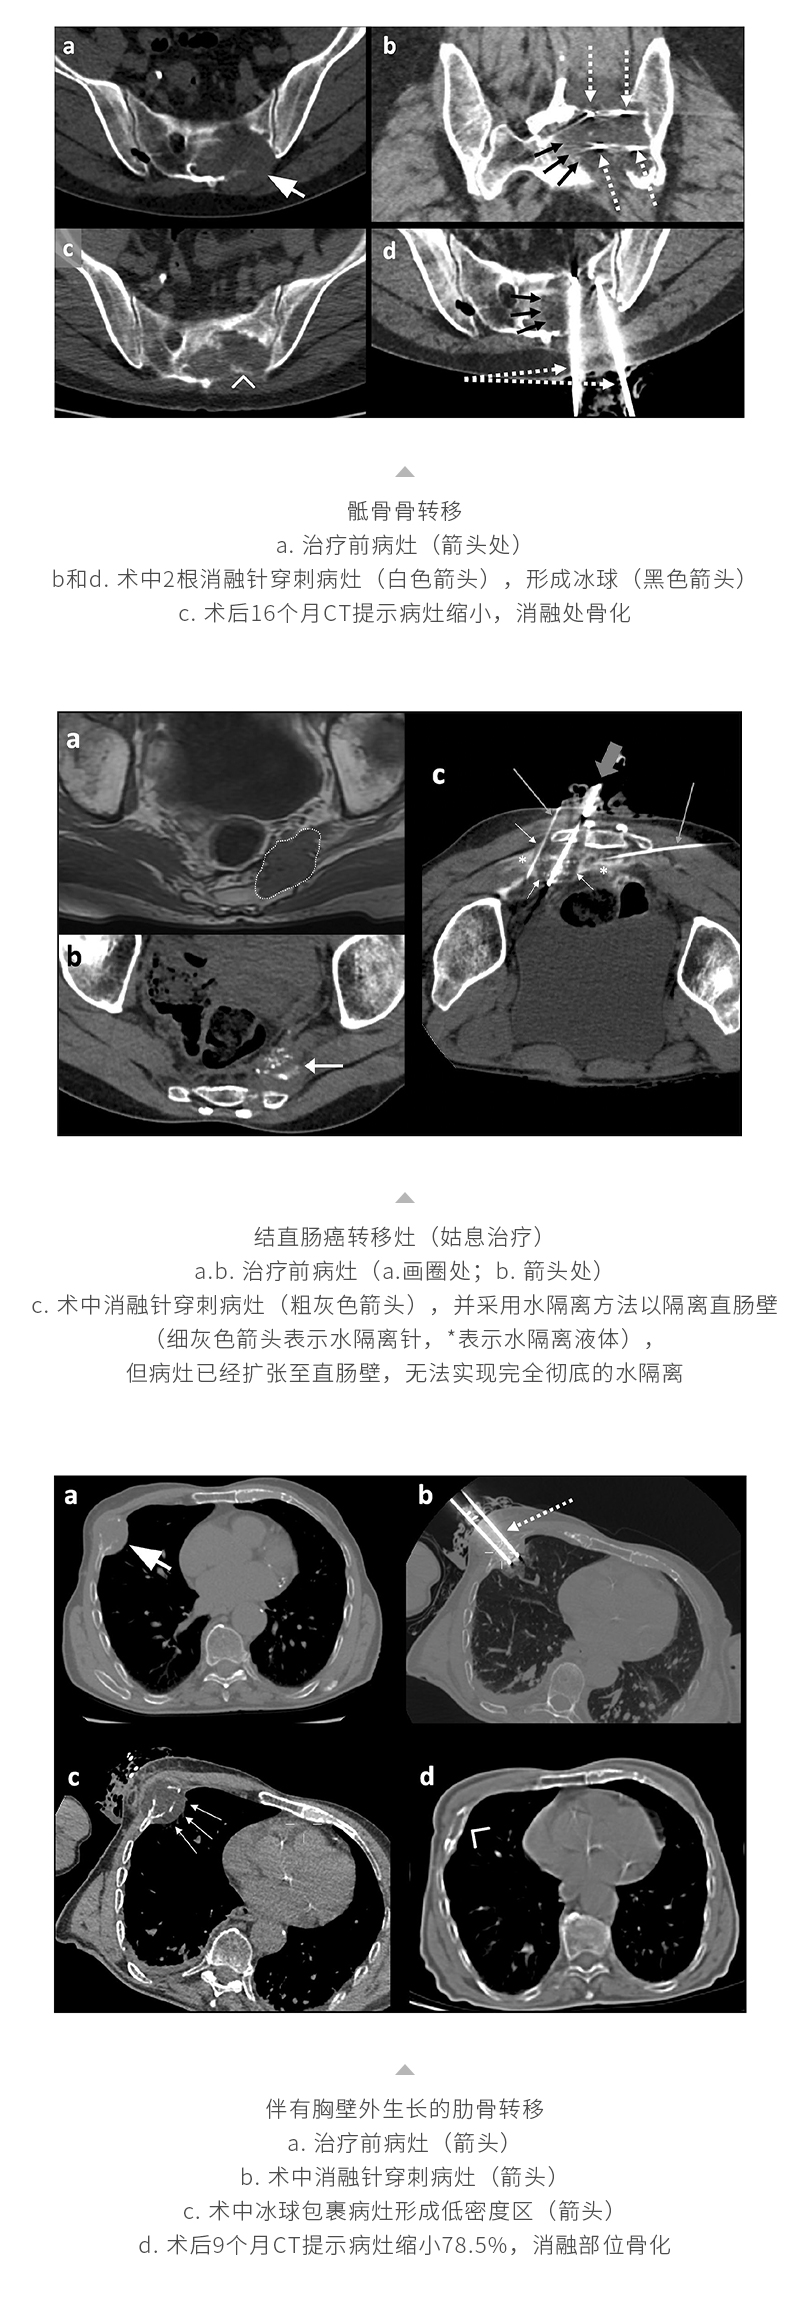

康博刀 ®

微波消融系统